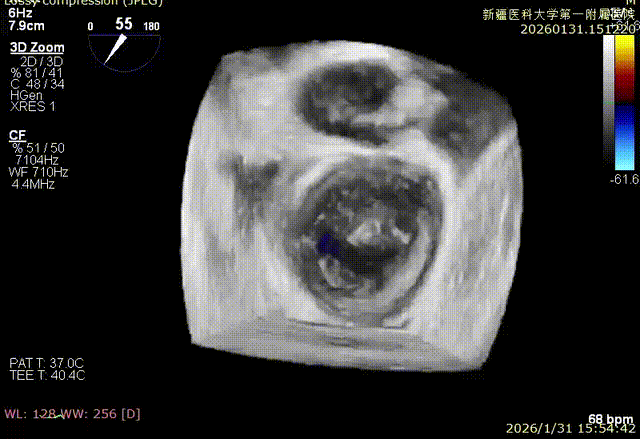

3D enface 切面

3D enface观察反流

3D enface 完成Orientation调整

3D enface反流充分降低

3D enface 观察后叶栓系